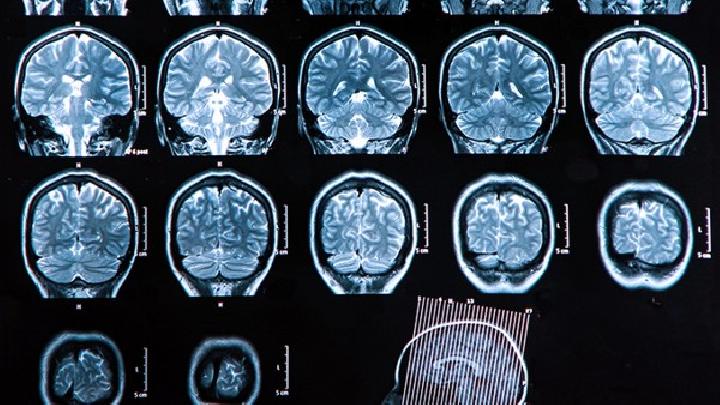

如今引发脑瘫的因素有很多,很多家长不注意使得自己的孩子患有脑瘫,从而给家庭笼上了一层阴影,让孩子也遭受疾病的折磨,下面我们就来详细的说说,孩子脑瘫危害有哪些,希望大家也做好脑瘫的预防工作。

综上述所就是脑瘫的危害有哪些的具体介绍了,女性在怀孕期间就要做好孕期检查,这也是防止腹中胎儿患有脑瘫的唯一方法,及早做好脑瘫的预防工作,减少疾病的发病率。相信大家在看完后都有了一定的了解,希望本文对您有所帮助。